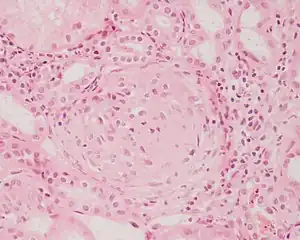

Glomerulonefrită

Termenul de glomerulonefrită face referire la inflamații renale, care în cazul care nu sunt tratate, pot cauza blocarea funcției renale. Cauzele acestor afecțiuni sunt bacteriile infecțioase ce trec din bazinet sau uretere. Aceste maladii pot fi și consecința unor maladii infecțioase ca inflamarea amigdalelor, scarlatina etc.